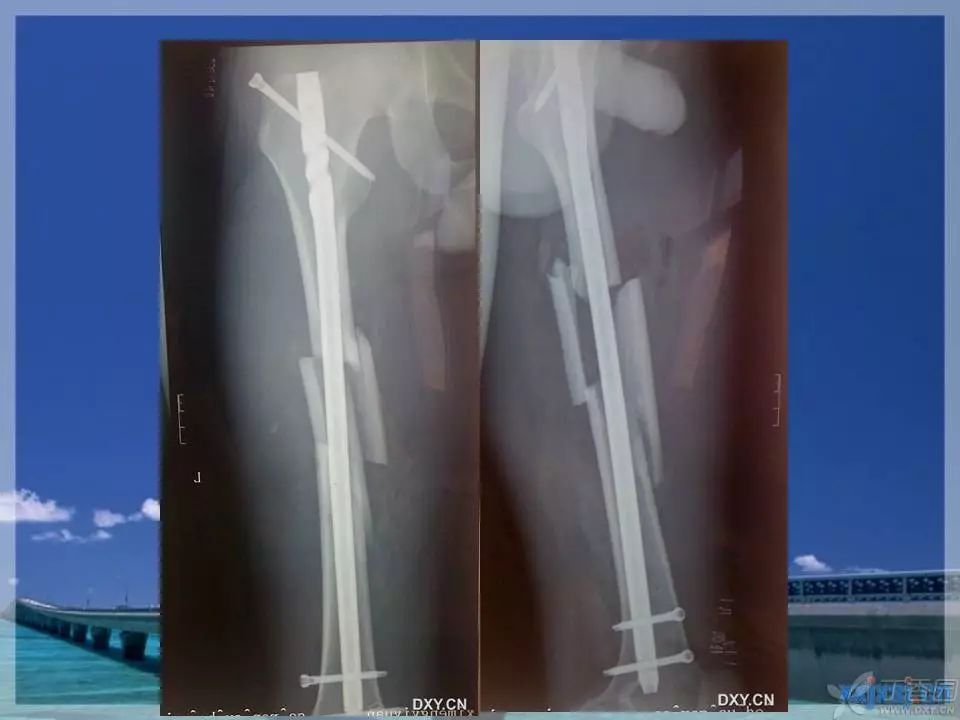

股骨干骨折是临床常见骨折之一,闭合复位髓内针固定治疗已成为首选。那么复位标准是怎样的?骨折块分离多少可以接受?钢丝可不可以用?不扩髓可以吗?相信看完下面这个课件你会有所收获~

1. ppt 中提到蝶形骨块移位大于 1cm 会影响股骨干骨折的愈合,这是一个台湾学者的观点,图中可以看见股骨内侧和后侧已经有骨痂生长,所以说 1cm 这个数据有待商榷。大于 1cm 的移位骨折愈合也不是什么问题。

2. 术前交待很重要,术前要交待患者及家属:如果把骨折对得严丝合缝,容易破坏骨折端的血运,而且手术时间长,出血多;而闭合复位虽然不能解剖复位,但是不破坏骨折块的血运,骨折更容易愈合。